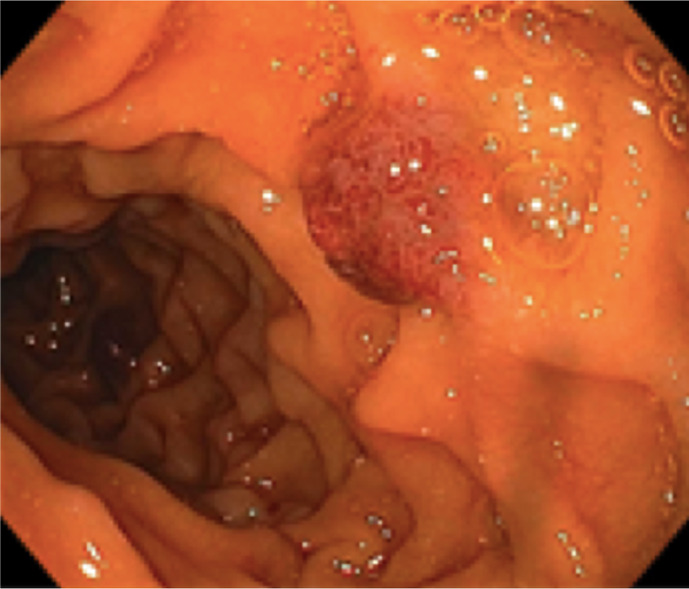

Case description: A 56-year-old male presented with 2 months of abdominal pain, distension, fatigue, and weight loss. Imaging revealed multifocal hypodense liver and splenic lesions. Laboratory findings included severe anemia (Hb 6.1 g/dL), thrombocytopenia (63 × 103/mm3), and elevated liver enzymes. Ascitic fluid analysis demonstrated exudative, bloody ascites (SAAG <1.1) without malignant cytology. Liver biopsy confirmed HAS, showing atypical spindle cells infiltrating vascular channels, positive for CD34 and factor VIII. Despite transfusions, paracentesis, and palliative care, the patient developed disseminated intravascular coagulation and died 2 weeks post-diagnosis.